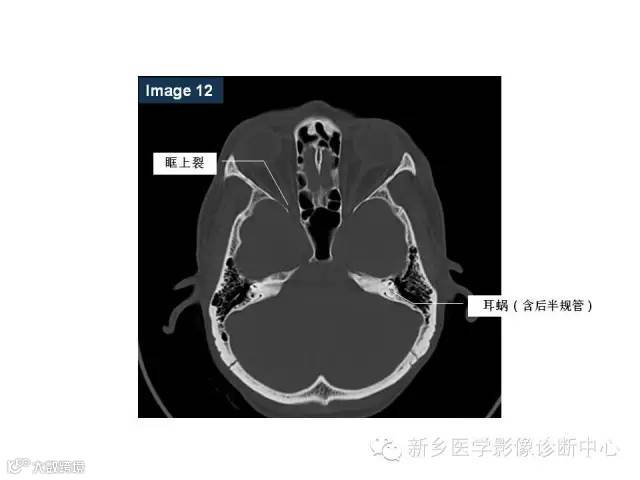

颅底孔道解剖详解

值得收藏!